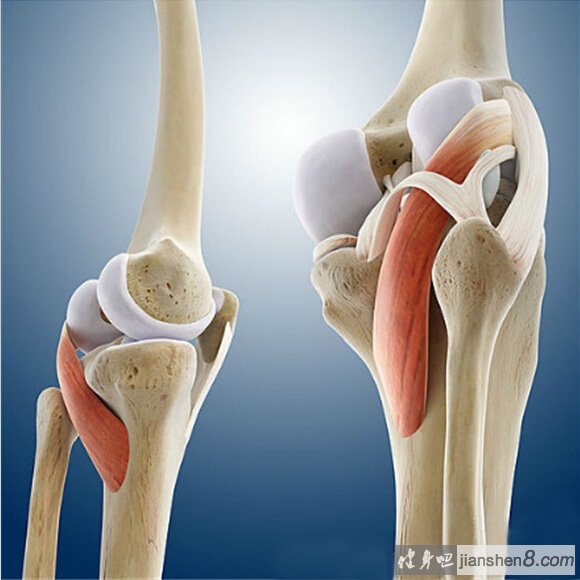

膝关节就像一台日夜运转的精密 “铰链机器”,关节表面覆盖着一层光滑如瓷的软骨,这层软骨质地柔软且富有弹性,能像缓冲垫一样减少骨头之间的摩擦,让膝盖在屈伸时灵活自如。而膝关节骨关节炎,简单来说就是这层软骨长期 “过劳” 后的 “老化反应”。随着时间推移,软骨会逐渐变薄、失去弹性,甚至出现碎裂和脱落,当软骨磨损到一定程度,下面的骨头就会暴露出来,原本宽敞的关节间隙慢慢变窄,走路时就会出现骨头磨骨头的情况,这也是疼痛的主要来源。